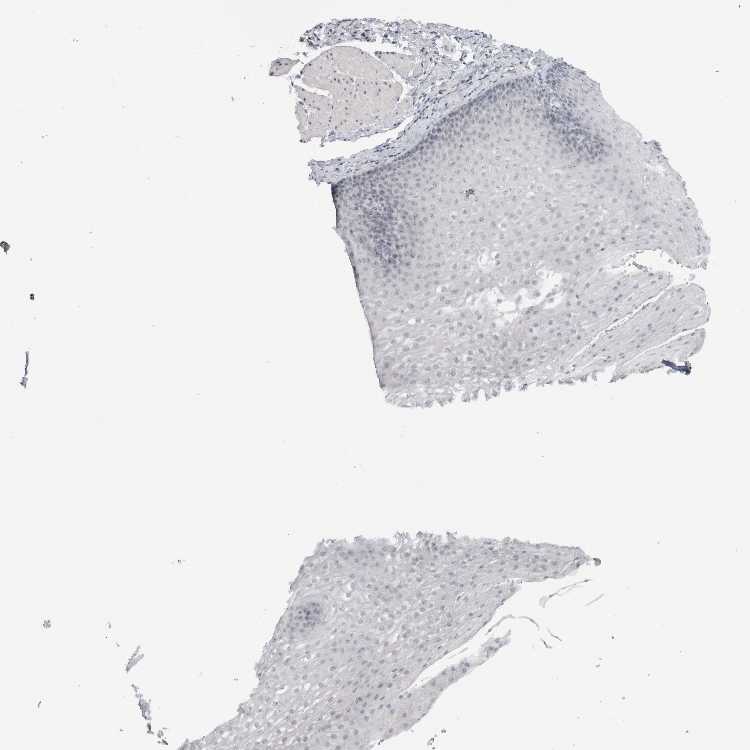

ESOPHAGUS - Antibody stainingi

Antibody staining in the annotated cell types in the current human tissue is reported as not detected, low, medium, or high, based on conventional immunohistochemistry profiling in selected tissues. This score is based on the combination of the staining intensity and fraction of stained cells.

Each image is clickable and will lead to virtual microscopy that enables deeper exploration of all samples and also displays staining intensity scores, fraction scores and subcellular localization as well as patient and tissue information for each sample.

Antibody HPA011284Antibody CAB026403

Squamous epithelial cells Not detectedNot detected